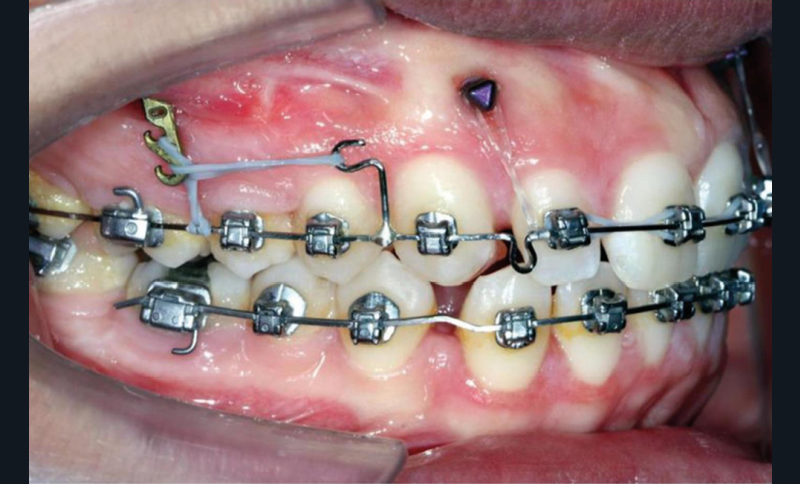

À côté de la coopération moindre qu’ils exigent, les ancrages squelettiques présentent également l’avantage de répondre à des indications très variées : correction des sourires gingivaux (Dr Skander Ellouze, fig. 3a-c), distalisation ou mésialisation molaire, supports pour les masques faciaux, mini transpalatin sur vis après expansion, ressorts de rétraction pour mettre en place les canines incluses sans léser les racines des dents adjacentes [3] (Dr Stéphane Renger, fig. 4) ou appareils d’expansion maxillaire (Dr Hans Winsauer, Dr Guido Sampersmans, fig. 5a-c)…

Ces dispositifs, utilisés comme ancrage direct ou indirect, répondent à une biomécanique particulière qu’il faut connaître pour en éviter les nombreux effets indésirables : bowing effect, versions, rotations (Dr Stefano Troiani)…